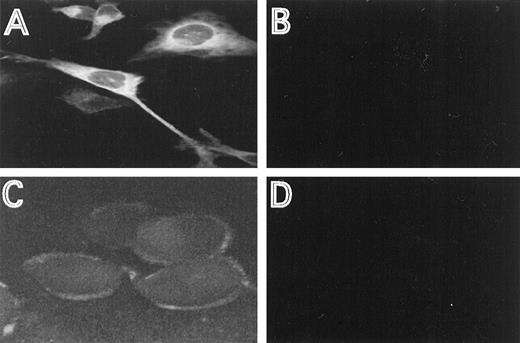

The cellular distribution of the induced HFE protein was analyzed by immunofluorescence, using HFE antisera directed against an N-terminal or C-terminal HFE peptide. In permeabilized cells, most of the staining occurred intracellular in a perinuclear location (Fig2A). This distribution is similar to the one described for the transferrin receptor.16 29 Using the antiserum directed against the N-terminal peptide, membrane staining was clearly detectable with nonpermeabilized cells, demonstrating that a distinct fraction of HFE is associated with the cell membrane (Fig2C). The specificity of the immunostaining experiments is demonstrated by the lack of fluorescence in cells repressed for HFE synthesis, under otherwise identical experimental conditions (Fig 2B and D).

Immunostaining of HFE. HtTA-HFE cells were grown on coverslips for 4 days in the absence (A,C) or presence (B,D) of 1 μg/mL doxycycline. Immunostaining was perfromed as described in the methods. Permeabilzed cells were incubated with the antiserum directed against the C-terminal peptide (A,B), unpermeabilized cells were incubated with the antiserum directed against the N-terminal peptide (C,D).

To investigate the role of HFE in cellular iron homeostasis, we studied the effects of HFE expression on transferrin iron uptake, IRP activity, and the expression of IRP target mRNAs. As a tool, we generated a stably transfected HeLa cell line that expresses HFE under control of a tet-sensitive promotor. With this cell line (HtTA-HFE), HFE synthesis can be almost completely turned off upon addition of doxycycline and be regulated by more than 2 orders of magnitude (Fig 1). The nontransfected cell line (HtTA) expresses only little HFE: (1) in Western blot experiments, no HFE-specific protein band was detected with either of the 2 peptide antisera; and (2) highly sensitive RT-PCR showed only faint HFE-specific signals after 50 amplification cycles (unpublished data, February 1998). Therefore, HFE synthesis can be strictly regulated by addition of doxycycline, making these cells a suitable model for studying HFE function. Consistent with observations in other cell systems,7,14 in the HtTA-HFE cell line most of the detectable HFE is localized intracellularly, with a distinct fraction localized at the plasma membrane (Fig 2). The staining pattern for HFE closely resembles the one obtained for the transferrin receptor (unpublished data, August 1998), in good agreement with the finding that it forms stable complexes with HFE.12 15